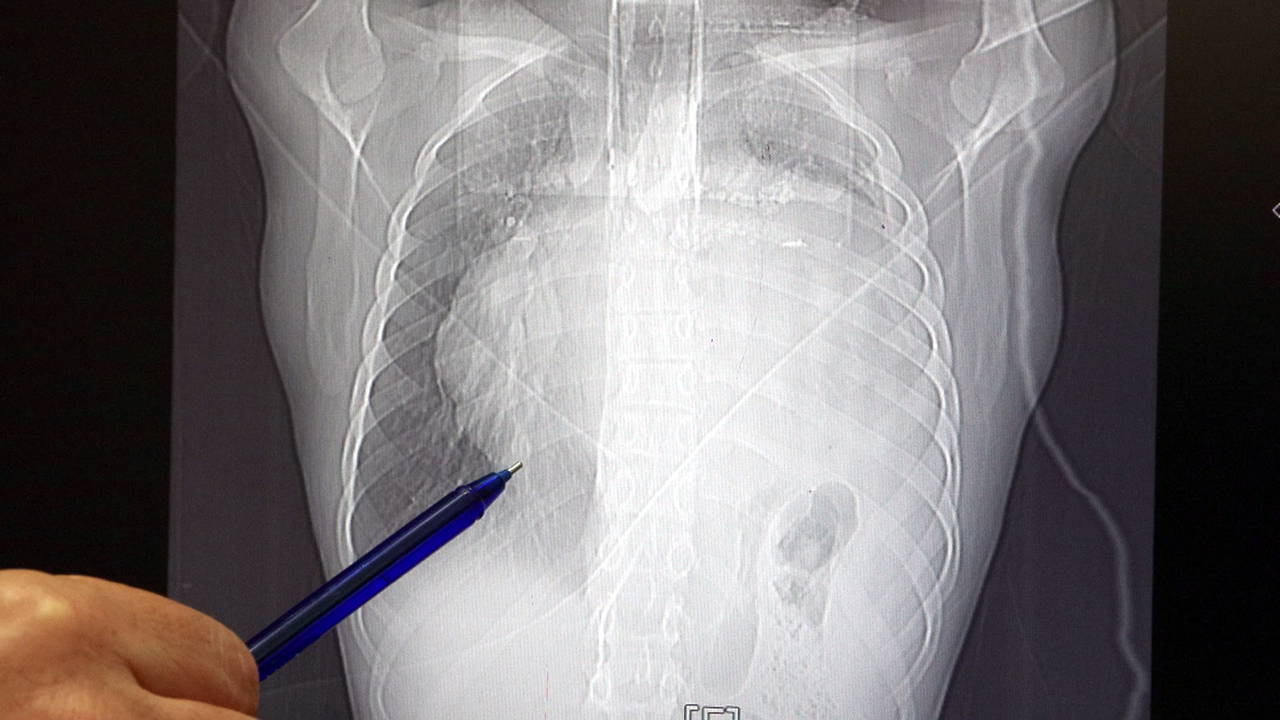

Kitleyi küçültmek için kemoterapi uygulansa da tam tersine tümör 2 ay içinde neredeyse 10 katına çıktı ve büyük bir karpuz boyutuna ulaştı. Sol akciğerinin yüzde seksenini kağıt gibi ezen, kalbini göğüs duvarında 12 santim sağa kaydıran ve hem kalbe hem beyne giden ana damarlara baskı yapan 6.5 kilo ağırlığındaki dev tümör, Göğüs ve Kalp Damar Cerrahisi ekiplerinin birlikte girdiği operasyonla başarılı şekilde çıkarıldı.

Prof. Dr. Erdal Taşçı, "Bundan 2,5-3 ay öncesine kadar hiçbir problemi olmayan, hayatını normal devam ettiren bir delikanlı Burak. Göğüs ağrısı öksürük ve nefes darlığı şikayetiyle sağlık kuruluşuna başvuruyor. Orada yapılan tetkiklerinde sol göğüs boşluğunda akciğerinden kaynaklanmayan portakal büyüklüğünde bir kitle tespit ediliyor ve immatür teratom tanısı konuyor. 2 ay arayla yapılan tetkiklerinde ve arada cerrahi öncesi küçültme amaçlı kemoterapi almasına rağmen, portakal büyüklüğündeki tümör, irice bir karpuz büyüklüğüne, yaklaşık 6 kilo 300 grama kadar ulaşıyor. Göğüs boşluğunda kemik kafesi içinde olduğu için, itebileceği iki organ var; biri kalp, diğeri de akciğerler. Soldan sağa doğru büyüdüğü için kalbi tamamen göğüs boşluğunun sağ tarafına itmiş ve kalbe giren ve kalpten çıkan bütün büyük damarları da yer değiştirmenin etkisiyle bükülmüş durumdaydı" diyerek açıklamlarına şu şekilde devam etti:

"Bu nedenle vücuduna yeterince kan gitmiyordu. Ağustos ayının başında portakal büyüklüğündeyken kitle Eylül sonuna irice bir kavun, Ekim ayına geldiğimizde ise bir karpuz büyüklüğüne ulaştığı için, kitlenin büyüme hızı bizi acilen ameliyat yapmaya yöneltti. Yaklaşık 8-10 kat hacimsel olarak artmıştı. Sol akciğer tamamen ezilmiş ve kağıt haldeydi, alt lobu anestezi ekibimiz yüksek basınç uygulayarak tekrar şişirdi. Çok fazla vaktimiz yoktu, kitle basısından dolayı yaşamla bağdaşmayacağından dolayı hızlı hareket etmek zorundaydık. Bize geldikten üç gün sonra hemen ameliyata aldık çünkü tümörden ziyade onun yaptığı baskıdan kaynaklı hayati riski vardı."